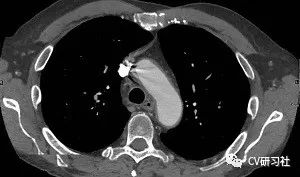

在医疗影像中做病灶体的检测: